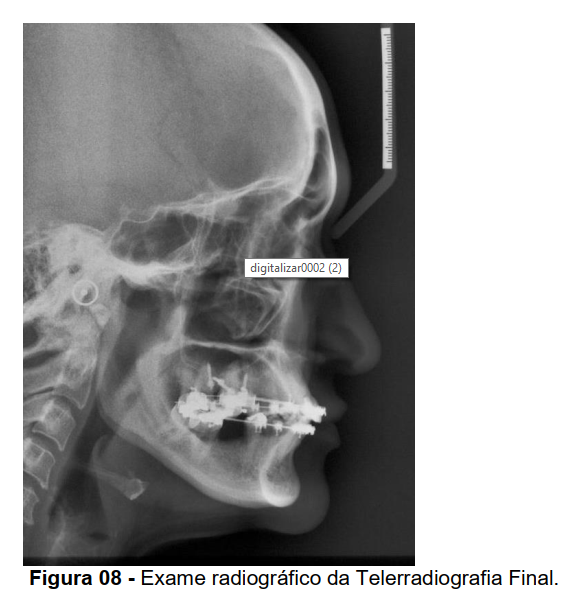

Após 18 meses de tratamento, foi verificada a intrusão necessária dos elementos 16 e 26 para a reabilitação protética do quadrante inferior esquerdo e direito conforme análise clínica e radiográfica complementares (Figuras 07, 08 e 09).

Nas telerradiografias inicial e final, foi construído o ponto centróide na coroa dos primeiros molares que sofreram intrusão com mini-implante. Uma linha vertical foi traçada perpendicularmente ao plano palatino unindo o mesmo ao ponto centróide (Figura 10). Desta forma pode-se medir a quantidade de intrusão dos primeiros molares superiores sendo que o dente 16 intruiu 3mm e o 26 intruiu 3,5 mm.

O centróide foi o ponto escolhido nos molares para que a quantidade de intrusão pudesse ser medida sem sofrer influência de movimentos indesejáveis como angulação e inclinação, ocasionando uma falsa idéia de intrusão. O ponto centróide representa o ponto dentário que menos sofre influência de possíveis efeitos colaterais por se tratar de um ponto sobre o eixo

longitudinal do dente. Além disso, utilizou-se o plano palatino como referência para medir a intrusão de dentes superiores (NG; MAJOR; FLORES-MIR, 2006).

Para avaliação de possíveis angulações dentárias, traçou-se uma linha passando pelo longo eixo do primeiro molar superior (LEM6S) formando um ângulo com a linha SN. O valor deste ângulo, medido nas telerradiografias inicial e final, permitiu identificar se o primeiro molar superior sofreu angulação durante a mecânica de intrusão (Figura 10). Neste trabalho a alteração com relação ao valor de inclinações dos molares foi insignificante demonstrando uma intrusão real destes dentes.